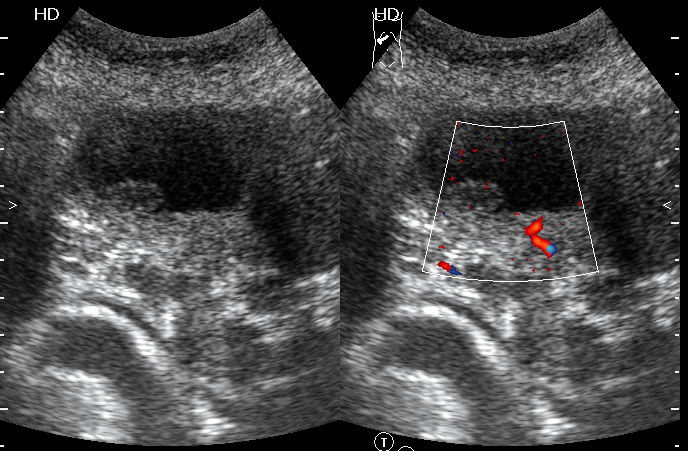

Женщина - пенсионерка. Жалобы скудные, дискомфорт в правом подреберье.